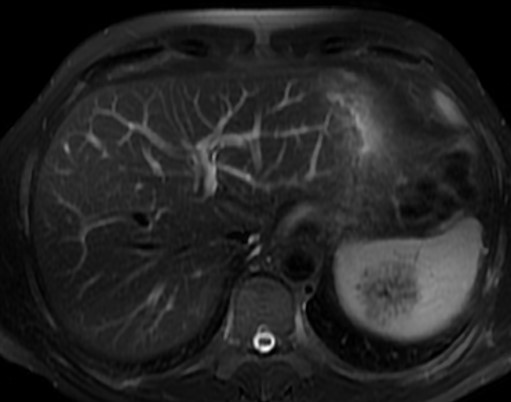

Paciente varón de 46 años con antecedentes de espondilitis anquilosante HLAB27+ y nefropatía crónica hipertensiva/tóxica, que acude a la consulta por dolor abdominal continuo en hipocondrio izquierdo de tipo opresivo de unos dos meses de evolución. A través de una ecografía se descubre una lesión esplénica de 50x60mm compatible con hemangioma. En la analítica se apreciaba leve aumento de urea y creatinina siendo el resto de los valores normales. Se completan estudios con TC y RMN (ver Figura 1) que fue informada como una masa sólida de 48x50x43mm, de baja intensidad de señal, heterogénea en secuencia T2, con múltiples imágenes lineales, sin restricción de la difusión y con captación progresivamente mayor hasta las fases más tardías del estudio, permaneciendo una región central hipocaptante. Estas imágenes eran compatibles con hemangioma vs otra lesión de estirpe vascular esplénica sin poder descartar otras posibilidades. El resto del estudio fue normal, sin adenopatías ni ascitis.

Figura 1. RMN: se aprecia lesión esplénica, sólida de aspecto heterogéneo.